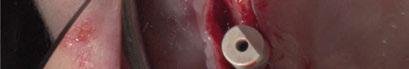

y lo que se pudo preservar del hueso malar. Se añadió una malla sinterizada infraorbitaria para dar volumen a la mejilla y se planificaron dos brazos de conexión que emergieran en las posiciones 24 y 26 de forma subgingival (Figuras 8 y 9). La superficie interna que apoyaba en el hueso era de titanio microrrugoso, y la superficie externa y conectores de titanio pulido y hexágono externo universal (Figuras 10 y 11). La cirugía se hizo bajo anestesia general en infiltración con anestesia local (4% articaína, 1:100.00 epinefrina), levantando el

colgajo cutáneo de la mejilla por vía intraoral, preservando el colgajo temporal para no comunicar con el remanente de la cavidad naso maxilar (Figura 12). Se emplearon 10 tornillos de osteosíntesis de 1,9 mm y la estabilidad primaria obtenida fue excelente (Figura 13)

4 meses después de la cirugía la encía estaba completamente cicatrizada y las conexiones de los implantes tipo hexágono externo universal quedaron a nivel yuxtamucoso. En este caso no se requirió el empleo de pilares transepiteliales y las impresiones fueron tomadas

Figura 10. Visión vestibular de la estructura con conexiones en titanio pulido.

Figura 11. Visión posterior de la estructura con titanio rugoso en contacto con el hueso.

Figura 13. Fijación del implante y emergencia de las conexiones.